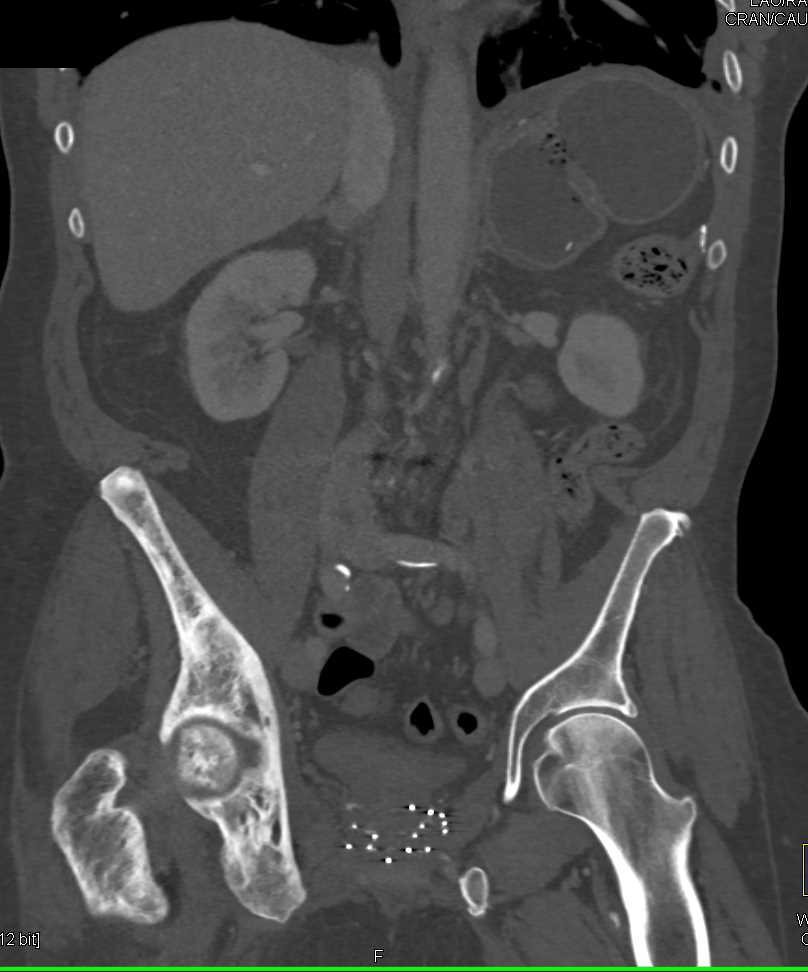

Paget's Disease Right Hemipelvis